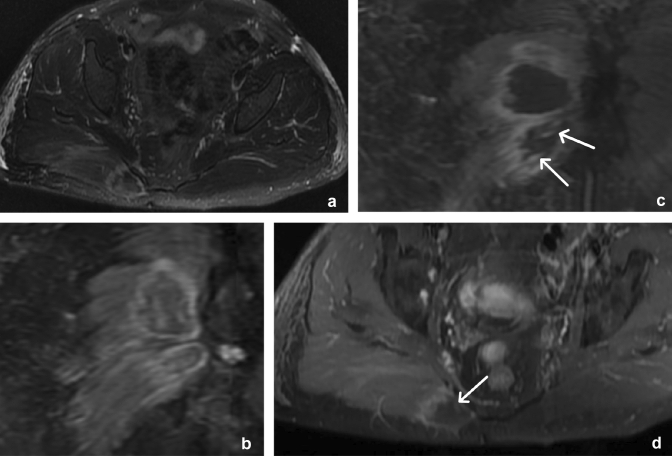

Hidradenitis suppurativa

Hidradenitis suppurativa (HS) is a chronic inflammatory skin disease involving the folliculopilosebaceous units and apocrine sweat glands and is also known as acne inversa. It has a female predominance and is associated with obesity, smoking, Crohn’s disease, and Dowling Degos disease and may be complicated by chronic sinus and fistula formation, epidural abscess from deep extension, osteomyelitis, and squamous cell carcinoma developing in chronic inflammatory tracts [41–43].

The disease typically affects apocrine gland-rich areas of the body, such as the genitofemoral area and axillae [42]. Imaging shows marked thickening of the skin, edema of the subcutaneous tissues, and formation of multiple small subcutaneous abscesses as well as sinus and fistula formation. It has a characteristic distribution, causing severe skin thickening which is typically bilateral and fairly symmetric along the perineum and gluteal folds (Fig. 21) or the axillary folds [44]. By comparison, simple cellulitis tends to have a more diffuse “fat stranding” appearance with more mild skin thickening. The involved areas are typically of soft tissue attenuation on CT, dark on T1, and bright on T2-weighted MR images with peripheral enhancement of subcutaneous abscesses (Fig. 22). MR imaging can be very helpful when HS involves the genitofemoral areas in patients with Crohn’s disease (who have an increased incidence of HS) to determine the cause of a peri-anal fistula, which can occur in both Crohn’s disease and HS. A recent study showed that while some MRI features of anoperineal disease may overlap between Crohn’s disease and HS, a specific diagnosis of HS is possible with a combination of three features: absence of perianal predominance of disease, absence of rectal wall thickening, and bilaterality of features [45].

Fig. 21.

30-year-old male with Hidradenitis Suppurativa (HS). Axial (a, b) and coronal (c) CT reformats through the gluteal cleft and perineum demonstrate nodular, bilateral, fairly symmetrical subcutaneous soft tissue thickening (arrows) with sinus track formation (arrowhead) in a patient with pathologically proven HS. Contrast these findings with a different patient with cellulitis. Axial (d) CT image illustrates diffuse “fat stranding” in the left greater than right gluteal subcutaneous soft tissues (curved arrows), compatible with cellulitis. A developing fluid collection is noted in the right gluteal subcutaneous tissues

Fig. 22.

49-year-old male with Hidradenitis Suppurativa (HS). Axial CT (a), sagittal CT (b), axial T1W (c), axial T2 fat-saturated (d), and sagittal post-contrast fat-saturated T1W (e) MR sequences demonstrate diffuse nodular skin thickening (arrows) along the scrotum, bilateral groin, medial thighs, posterior buttocks, and lower back with linear high T2 signal suggestive of sinus tracks (arrowheads) and areas of superimposed enhancement which may represent superimposed infection or micro abscesses (curved arrows)